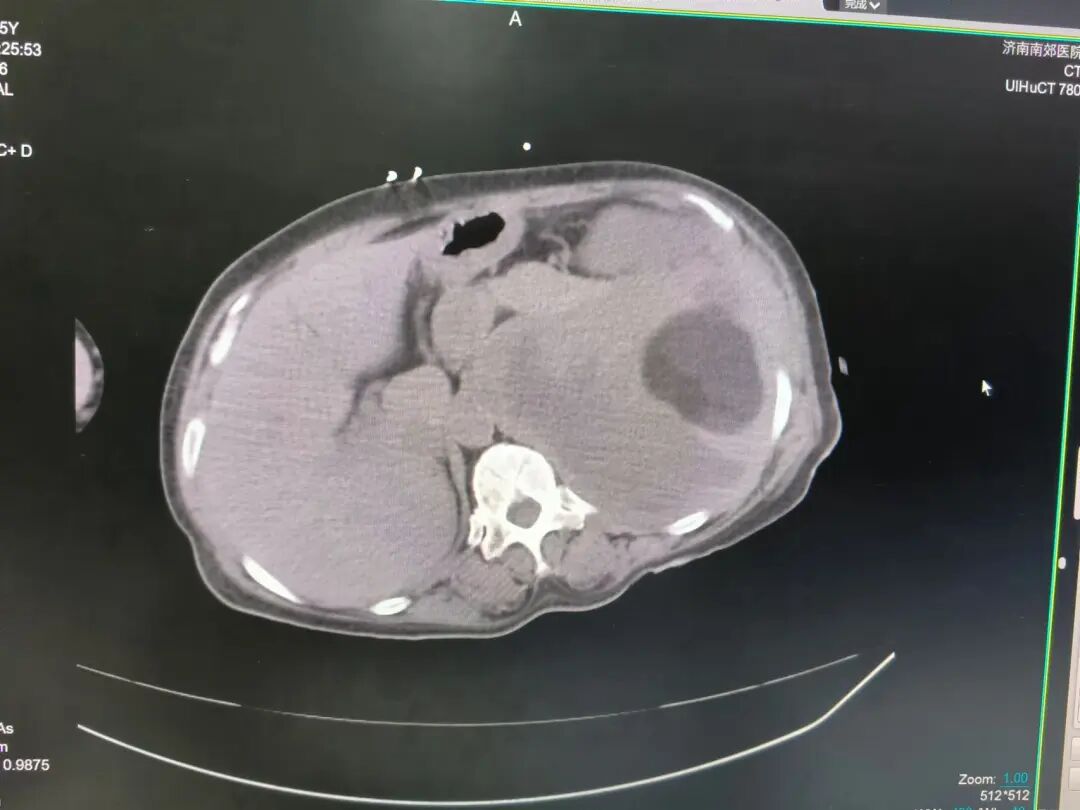

患者因腹部剧痛首次确诊腹腔肿物,手术切除后病理提示“间叶源性肿瘤”。然而,术后复查犹如一记重锤——手术部位再发肿瘤!二次切除后,北京某医院最终明确病理诊断:恶性外周神经鞘瘤(FNCLCC2级),一种具有侵袭性强、易复发特征的罕见软组织肿瘤。更棘手的是,此次肿瘤已压迫胃部,导致患者进食困难、体重骤降,传统手术与放化疗方案均面临巨大风险。

1、精准定位,直捣病灶:在CT引导下,消融针精准穿刺至肿瘤核心,避开周围正常组织;